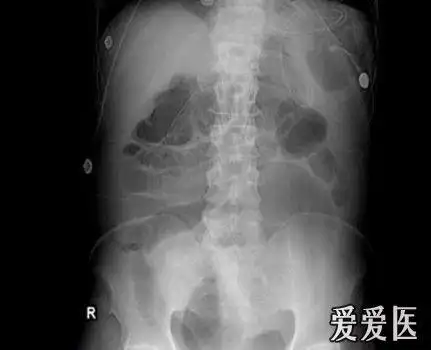

急诊腹部平片肠扭转大肠梗阻中毒性巨结肠腹膜后积气